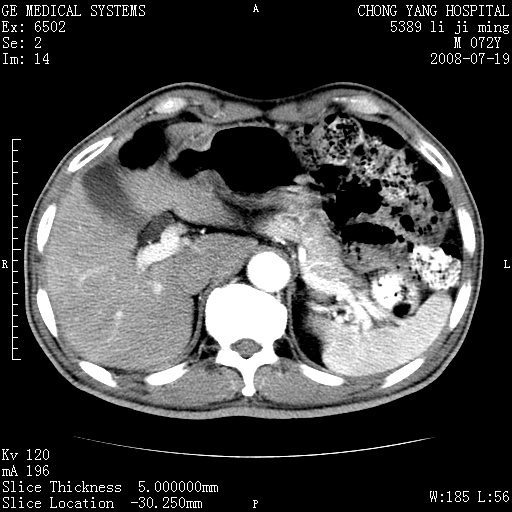

以下是引用zjzjr在2008-7-19 20:57:00的发言:[br]胰头增大,边缘模糊,周围可见渗出影,右侧肾前筋膜增厚.支持胰腺炎.

以下是引用yangyudong333在2008-7-20 6:56:00的发言:[br]胰腺增大尤以胰头明显,边缘模糊,周围可见渗出影,右侧肾前筋膜增厚,肠管於涨.支持胰腺炎

以下是引用不学无术在2008-7-19 23:15:00的发言:[br]胰腺增大尤以胰头明显,边缘模糊,周围可见渗出影,右侧肾前筋膜增厚,肠管於涨.支持胰腺炎